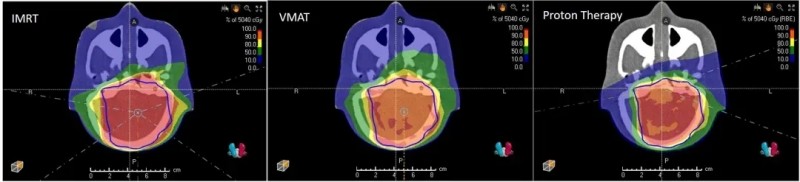

因此,儿童肿瘤放疗需尽可能减少健康组织暴露,质子治疗也被视为儿童癌症的首选放疗方式——它能在精准抗癌的同时,最大限度降低晚期放疗副作用,有效避免儿童出现智商下降、生长迟缓、发育障碍、继发性肿瘤等长期伤害(下图为传统放疗[调强放射治疗(IMRT)、容积调强放射治疗(VMAT)]与质子治疗(ProtonTherapy)的器官暴露剂量对比)。

▲图源“frontiers”,版权归原作者所有,如无意中侵犯了知识产权,请联系我们删除